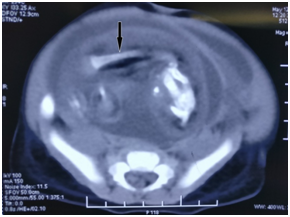

A 5 month old boy was admitted to Department of Pediatric Surgery, BSMMU on May 2017. At the age of 1 and half months, his parents noticed a lump in hislower abdomen. The lump is gradually increasing in size and is not painful. The boy has occasional vomiting but no other complains. The mother wasn’t on regular antenatal checkup however there was no history of any maternal illness, exposure to radiation or drug intake during pregnancy. There was no family history of multiple pregnancies. The boy was delivered by cesarean section as he was postdated. His postnatal period was uneventful. On clinical examination, there was a 10x10cm, well-defined, firm, non-tender, round mass occupying the right lumbar region, right iliac fossa, umbilical, hypogastric region and left iliac fossa. Laboratory investigations were within reference ranges. Alpha-feto protein was 36.25ng/ml (up to 15 ng/ml) and beta-HCG was 0.34mIU/ml (within normal range). Ultrasound of abdomen showed a large complex mass having solid, cystic components located on the lower abdomen. It measures about 10.6x9.0 cm. the mass is separated from right kidney. Also, in kidney, pelvicalyceal system are moderately dilated but cortex medulla are well defined. CT scan reported one fetus measuring about 12x11 cm is noted in the pelvic cavity and right lumber region having deformed skeleton within. The lesion is displacing the bowel, bladder and compresses the kidneys and ureters posteriorly. CT scan also reported moderate hydroureteronephrosis. A preoperative diagnosis of fetus in fetu with moderate hydroureteronephrosis was made (Figure 1 & Figure 2).

Figure 1 CT scan of the patient’s abdomen reveals a large retroperitoneal soft tissue mass. There are long hypodense opacities that resemble fetal bones (see arrows).